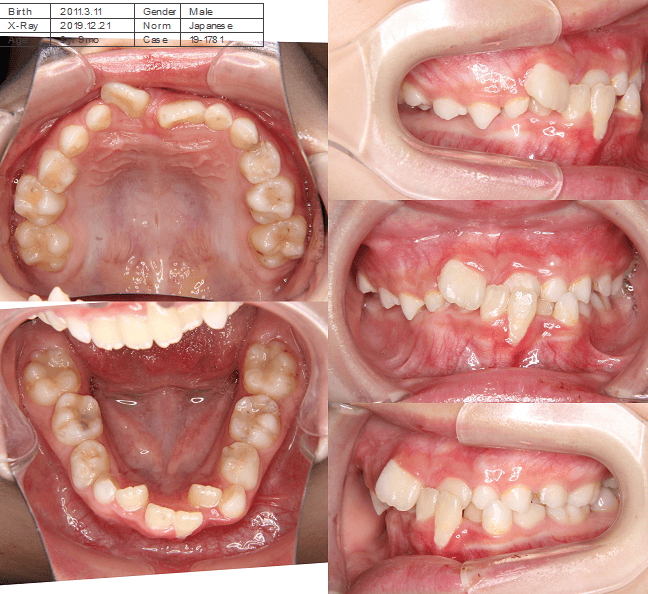

早期矯正治療 叢生症例①

主訴 | 歯の生えるスペース不足が懸念され、歯列の乱れ(叢生)を整えるために来院された患者様です。 |

---|---|

診断結果 | 7歳1か月の男児。 叢生の進行が見込まれると診断されました。 |

治療内容 |

|

治療後の経過 | 1年3か月の動的治療を通じて、上下顎の歯列が改善されました。 治療終了後は3〜4か月に一度の定期検診を継続しており、本格矯正治療の開始時期を判断していく方針です。 |

治療期間 | 動的治療期間:1年3か月 通院回数:11回 |

治療費用 | 420,000円(税別) |